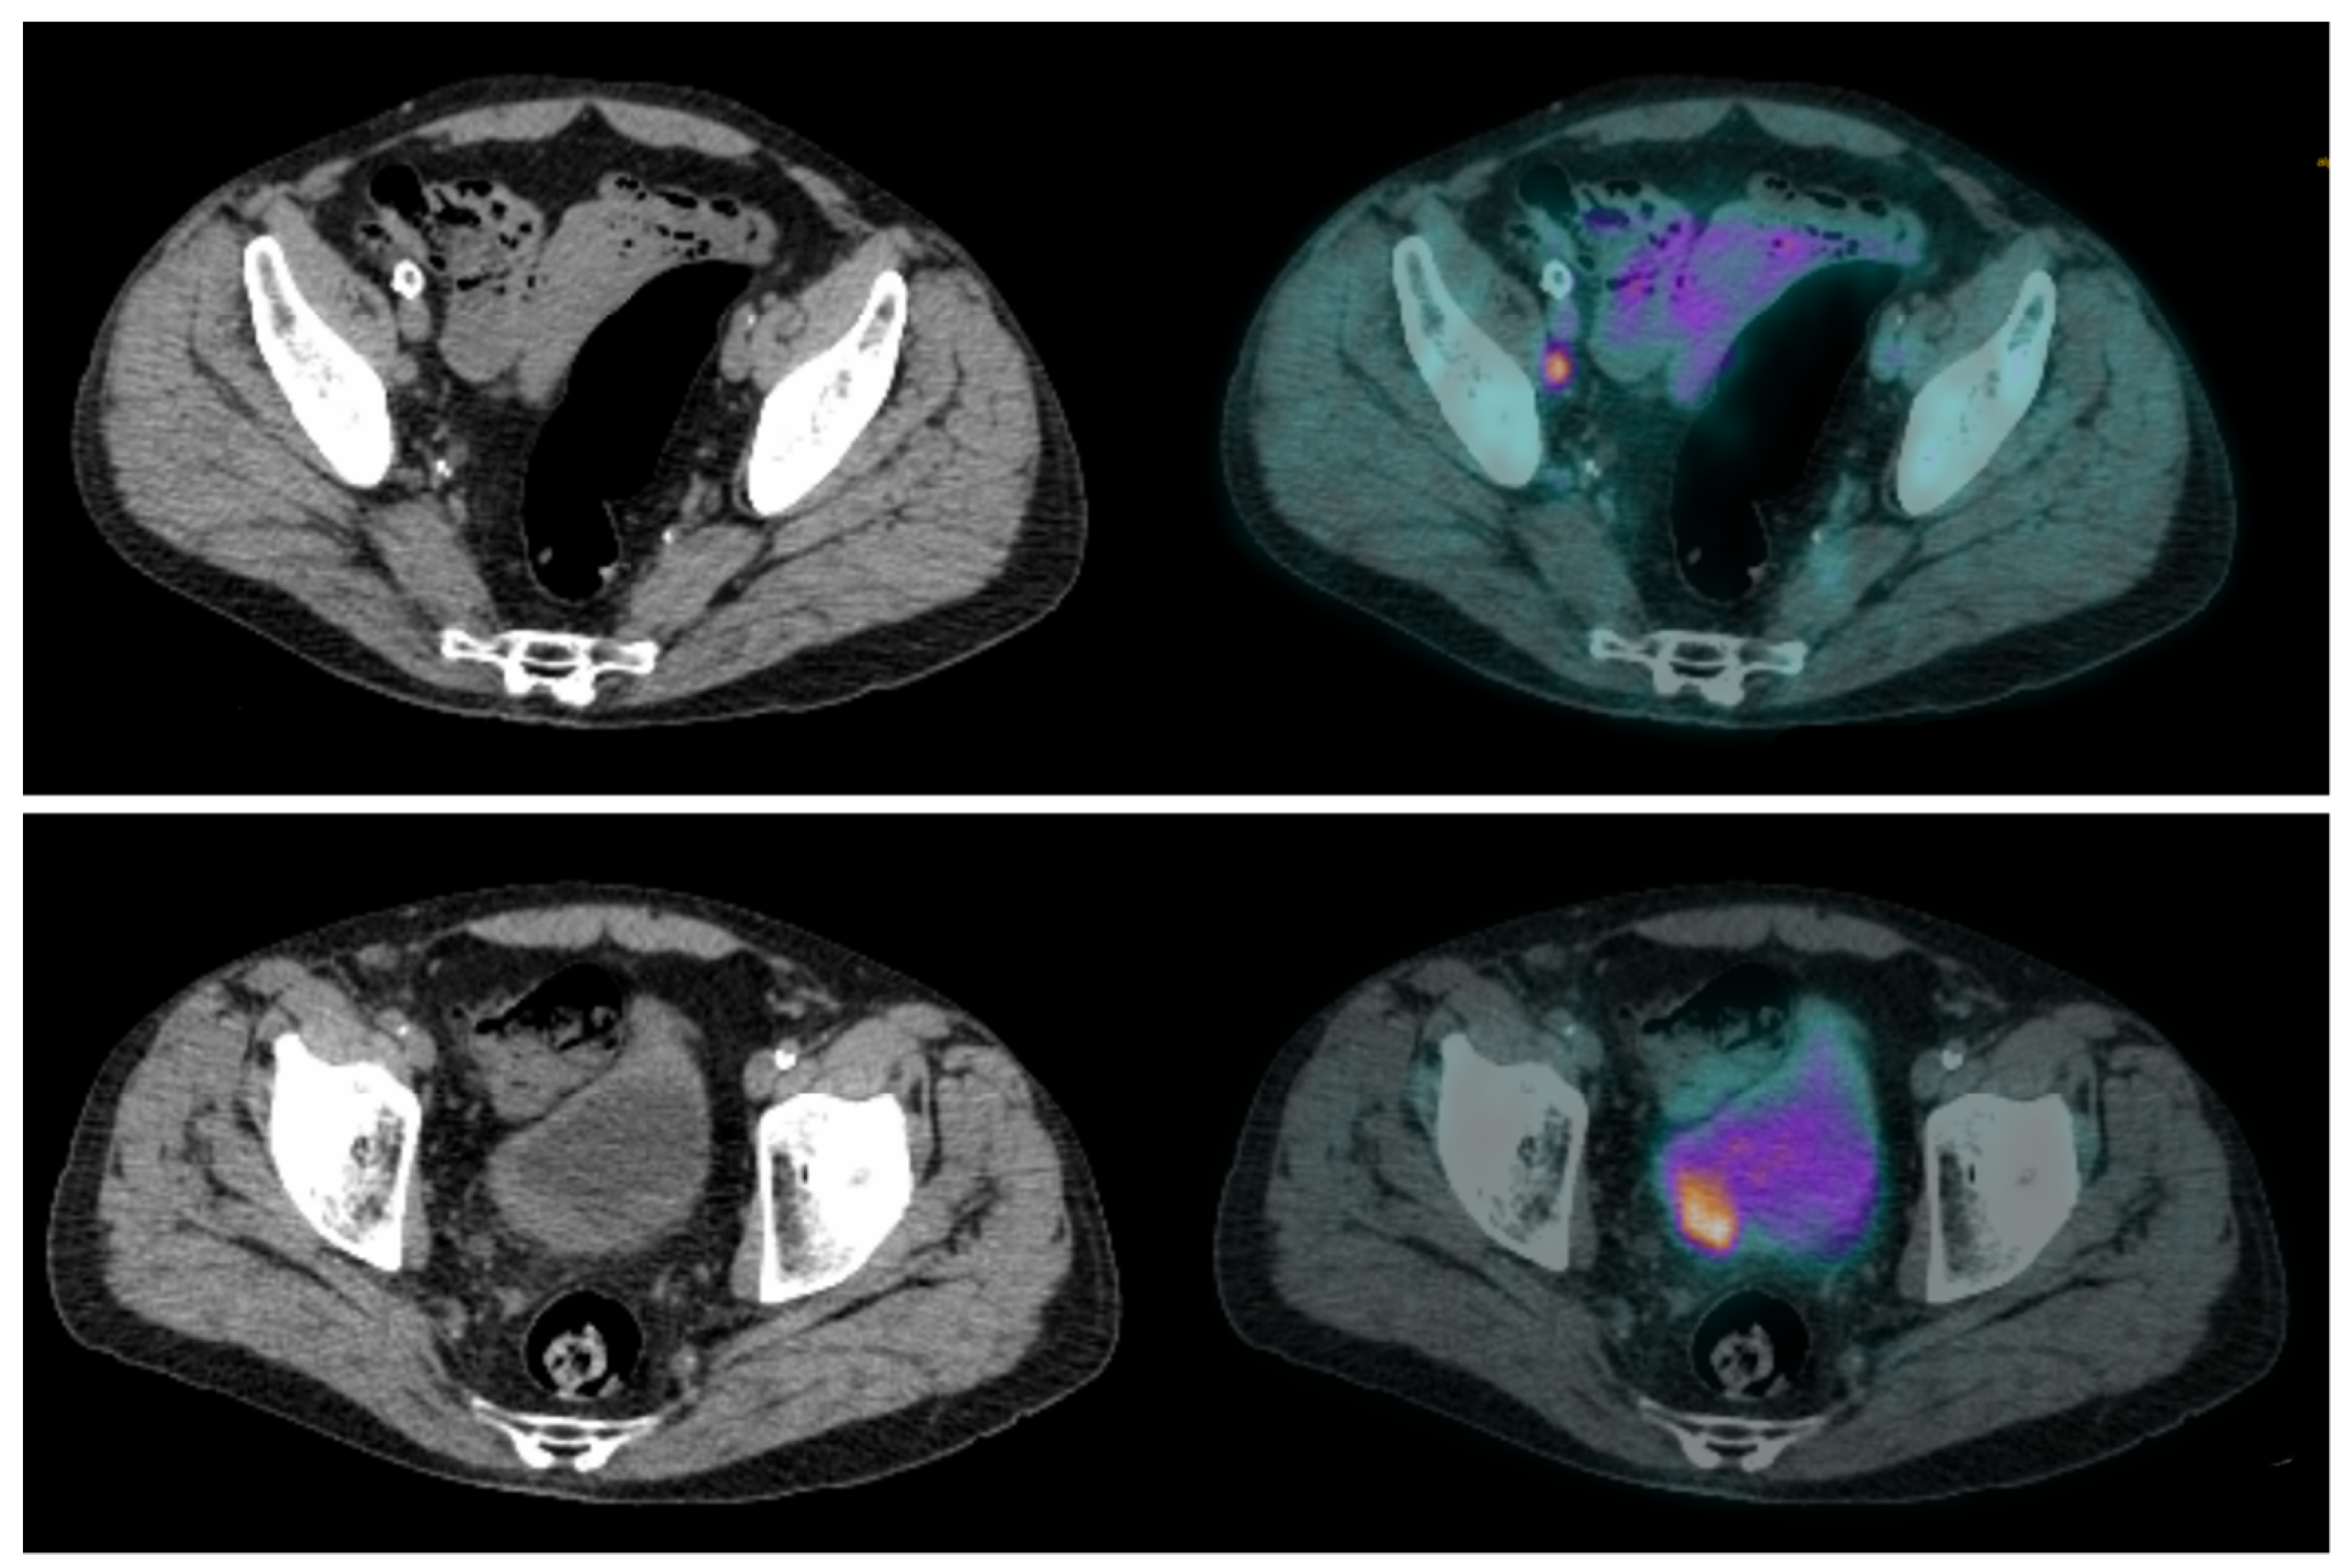

- Rouanne, M.; Alhammadi, A.; Vilain, D.; Radulescu, C.; Lebret, T. Value of positron emission tomography in diagnosing synchronous penile metastasis from urothelial bladder cancer. World J. Surg. Oncol. 2015, 13, 276. [Google Scholar] [CrossRef]